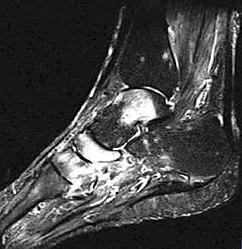

Um ein Knochenmarködem festzustellen, muss eine Magnetresonanztomografie (MRT) durchgeführt werden. Diese Flüssigkeitsansammlung unter der Knochenhaut verursacht starke Schmerzen, die auch ohne Belastung des betroffenen Bereichs anhalten können.